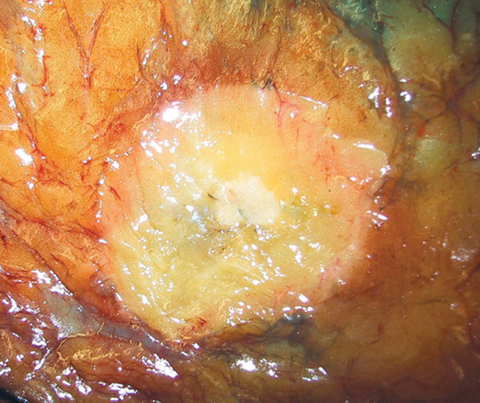

Gross description

- Grossly evident mass, with an irregular, stellate outline or nodular configuration

- Mass is usually poorly circumscribed and contracts from surrounding tissue

- Firm or even hard on palpation and may have a gritty feel when cut with a knife, grating sound when scraped

- May show streaks of chalky white elastotic stroma penetrating surrounding stroma (crab-like), calcification

- Large tumors have hemorrhage, necrosis and cystic degeneration

- May be fixed to chest wall and cause skin dimpling or nipple retraction

- Some tumors, including neoadjuvant treated cancers, may be grossly inapparent and require careful correlation with the imaging at the time of gross examination and tissue sampling